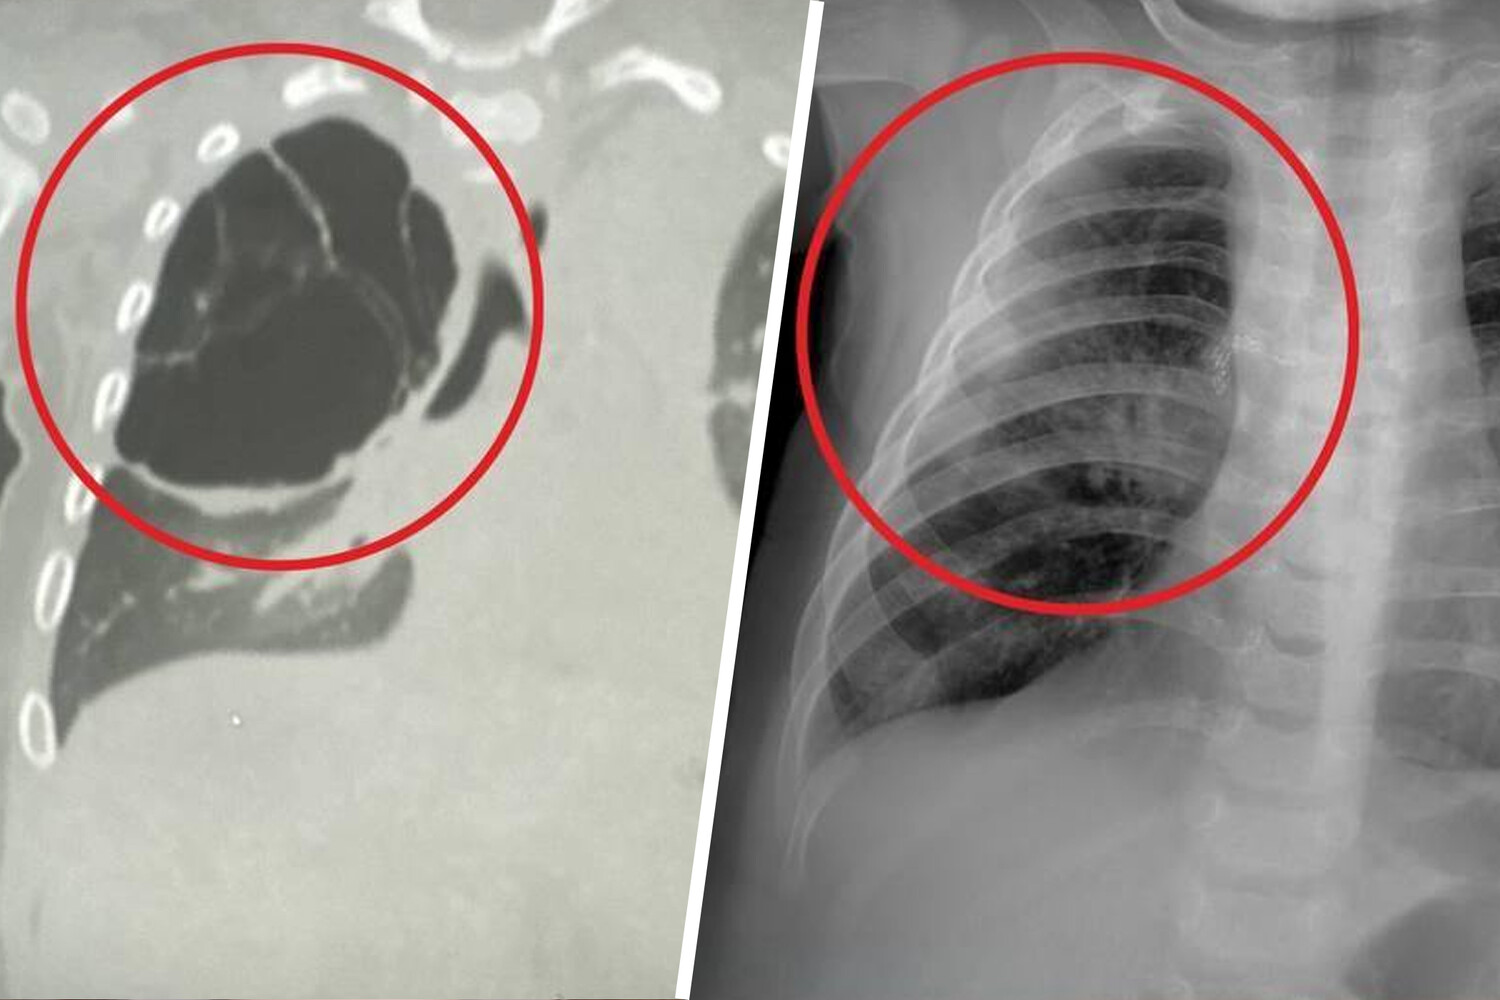

Как рассказали медики, образование было обнаружено во время воспалительного процесса, вызванного острой респираторной вирусной инфекцией. Киста занимала большую часть правого легкого ребенка и не давала ему полноценно развиваться. Врачи приняли решение удалить образование.

«Детские хирурги провели торакоскопическую операцию: без разреза аккуратно удалили кисту вместе с пораженной частью верхней доли правого легкого», — поделились в минздраве.

Операция длилась около часа и завершилась благополучно. Размер кисты составил около 15 сантиметров.